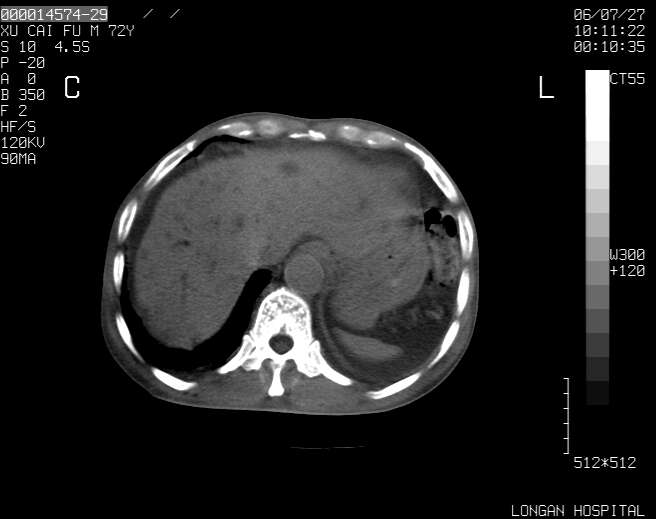

以下是引用winter在2006-7-30 20:14:00的发言:[br]1、考虑胆囊癌伴胆道侵犯并高位胆道梗阻、肝内多发转移、腹膜后淋巴结转移。[br]2、右肾轻度积水。[br]3、老人家72岁了胰腺头体尾部均较饱满,不过未见密度异常及其他异常征象。[br]4、腹水。

以下是引用jiajie在2006-7-31 7:10:00的发言:[br]考虑肝转移瘤,腹膜后淋巴结增大。[br]胃癌不能除外,建议胃镜检查。